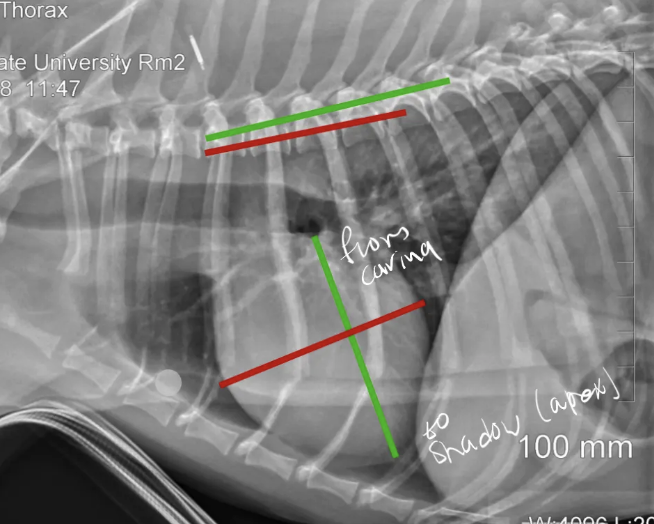

three ways that can help estimate the cardiac size?

A

1. evaluate cardiac height and width on the lateral view

2. evaluate carina on the lateral view

3. evaluate cardiac width on DV/VD

carina?

cartilaginous ridge at the bottom of the trachea where it splits into two bronchi

vertebral heart score (VHS)?

1. measure the long axis and short axis of the heart on a lateral view

2. align those lengths against the spine (starting at T4), and summing the vertebral lengths

(long axis) - from carina to apex